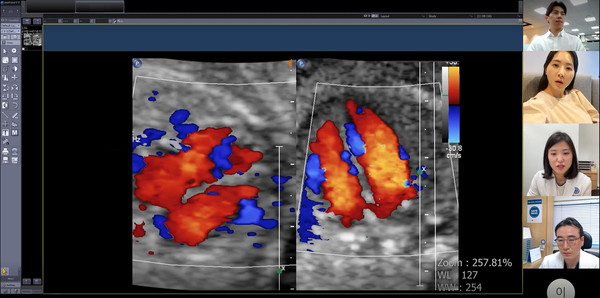

스마트 맘 케어는 산모와 태아의 안녕을 위해 1-3차 의료기관간 비대면 협진스시스템을 구축했다. 산모가 1차 의료기관에서 진료를 보더라도 증상이나 검사 결과 등 추가적인 관리가 필요할 경우 MS Teams를 통해 환자와 보호자, 1-3차 의료기관 의사가 참여한 화상협진을 통해 검사 결과에 대해 의견을 나눌 수 있다.